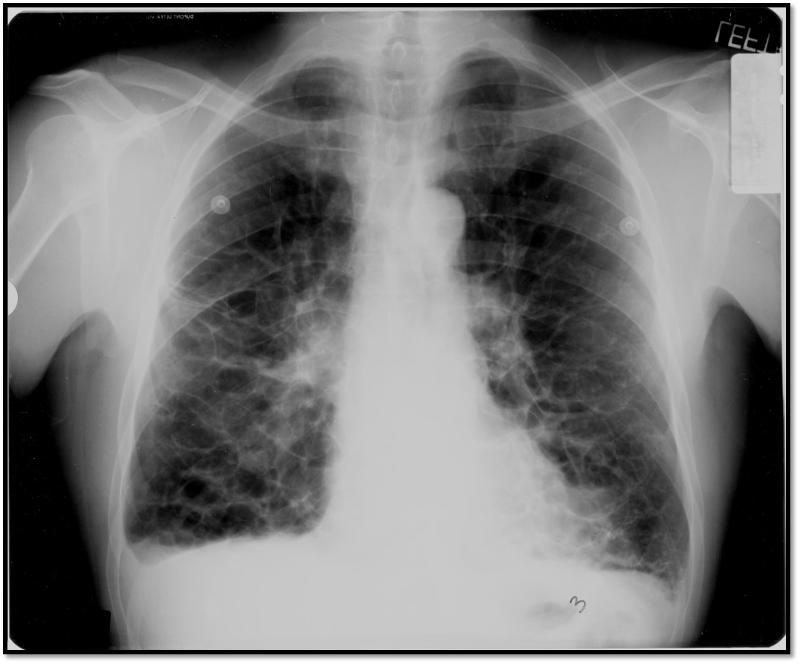

Air Space Disease. Details: Air space disease: The term airspace disease is generally used to indicate a problem involving the alveoli or air sacs in the lungs. Air space lung disease is an unofficial term that refers to air caught in the space between the outside of the lung and the inside of the chest cavity, between the pleural layers that are normally air tight. air space disease.hmmmm.

The purpose of this unit is to demonstrate the appearance of air space disease in the lungs.

The pulmonary acinus is the basic structural unit of the lung involved in gas exchange. Emphysema is the disease in which the air sacs in your lungs collapse. When you think of the causes of consolidation Honeycombing is defined by the presence of small cystic spaces with irregularly thickened walls.